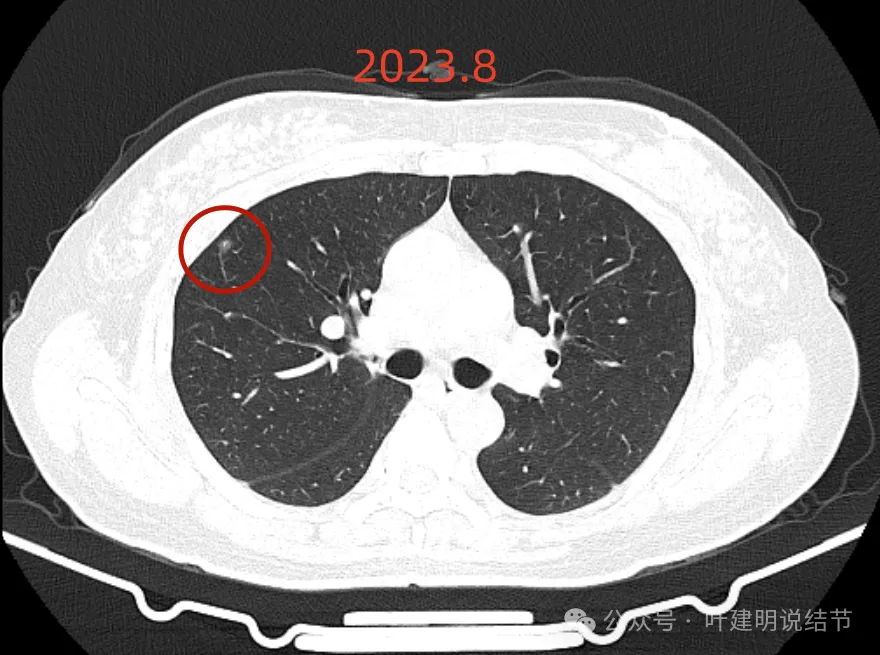

再看2023年8月时复查的影像:

有变化吗?说不上!

点击阅读:问诊分析(2023.9.23):这个于1年多前在国内某著名医院被我叫停手术的肺结节病人,现在怎么样了?